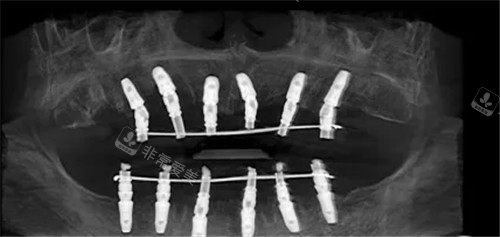

全口种植ct图片

手术方案:采用穿颧种植 8 颗植体的方案。

这种方案对医生的技术要求非常高,但能有效解决全口牙槽骨吸收患者的种植难题。